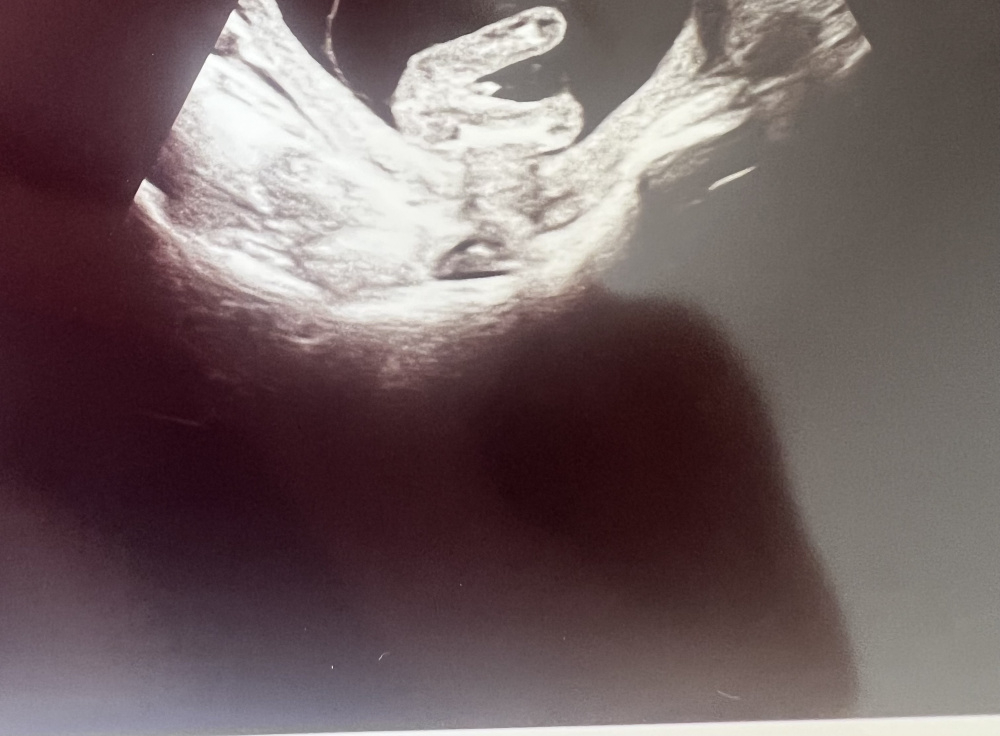

Hallo meine Lieben, waren heute beim Ultraschall SSW17

Das Geschlecht spielt bei uns keine Rolle, da wir bereits einen Jungen und ein Mädchen haben.

Aber aus reiner Neugier, was meint ihr anhand der Bilder, Mädchen oder Junge